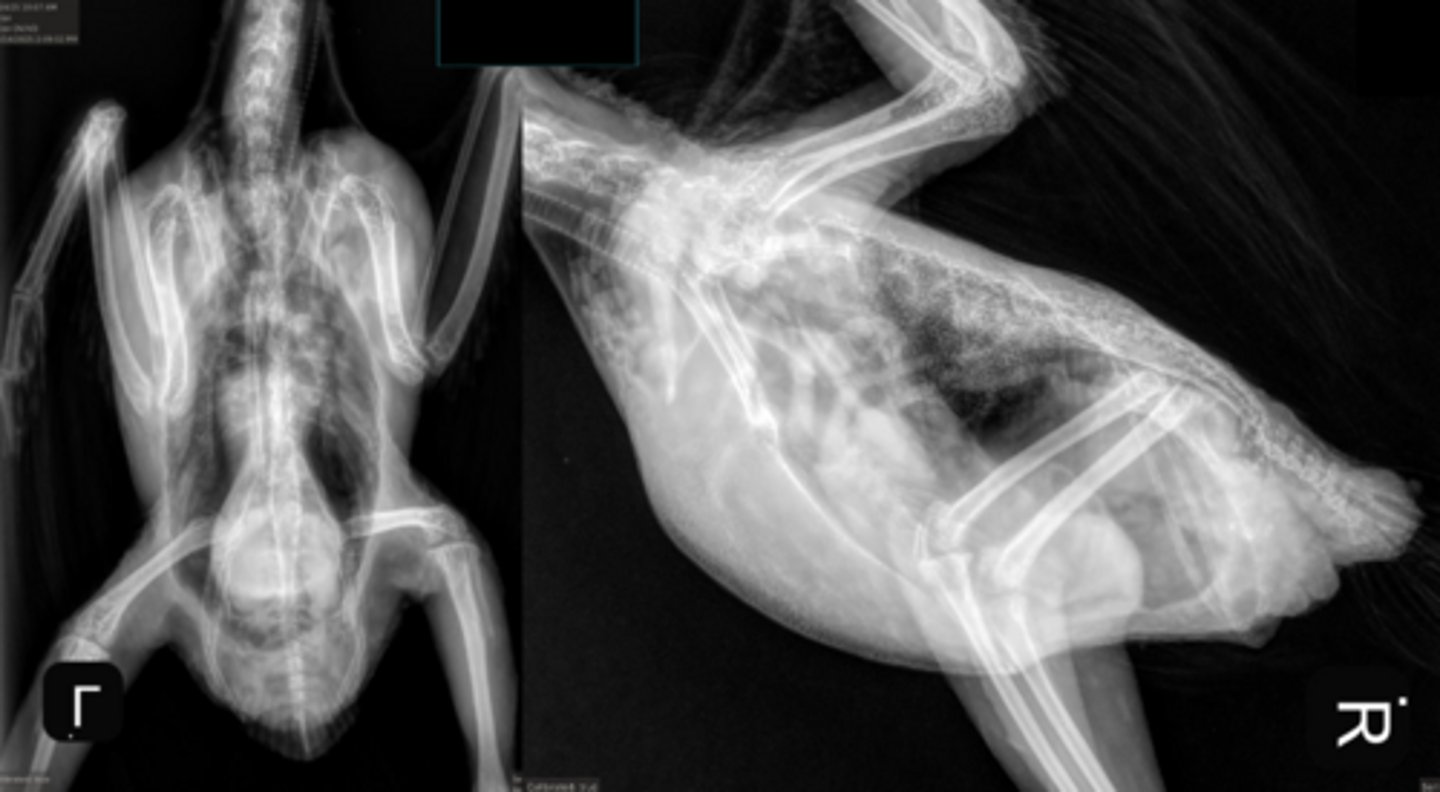

Radiographs

What is the #1 test to see if birds are egg bound?

1. number of eggs

2. position = want pointy end facing south

3. shell quality = there is not a "ghost shell" meaning no hypocalcemia in this bird, margin smooth and appropriate

4. bone quality of mother = polyostotic hyperostosis, bird is taking Ca from bones and putting into egg under influence of estrogen (normal to a point)

THIS BIRD IS NOT EGG BOUND

What are some factors you want to look at on radiographs to determine if the bird is eggbound?

1. multiple soft tissue nodules located in the area of the kidney, these are ovarian follicles

2. there are abnormal tissue "spheres" where the air sacs should be with irregular "eggs" that will probably not come thru on their own

3. metal or mineral opacity in crop (esophagus diverticulum) and ventriculus (gizzard) causing dorsocaudal displacement of the mass above it

Describe some things you are seeing in this bird

1. ostotic hyperostosis of the radius and ulna = physiologic, mostly normal for repro process under influence of estrogen

2. egg telescoped inside another in the caudal region of the coeloem

3. coelomic enlargement, more fluid than expected

4. especially visible on VD, soft tissue mass on lateral side around the level of the pelvis

Describe some things you see in this bird